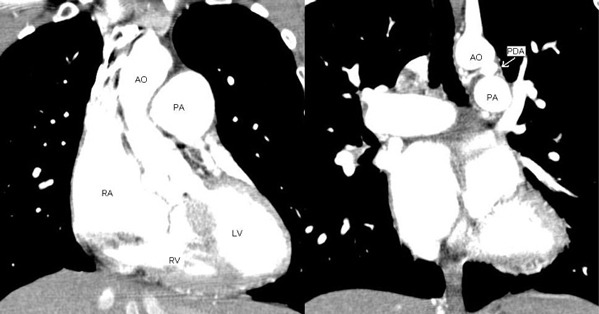

図6: 造影CT検査、画像を連続して分析すると、動脈管が大きく拡大し大動脈―肺動脈への血流を認める。

図7: 造影CT検査、3D画像を構成すると、大動脈と肺動脈の間に拡張した動脈管をみることができる。